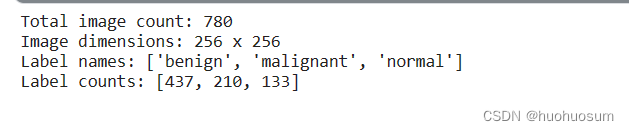

运行结果如下:

从图中可以看出,整理后的数据集分为 三类,一共有780张图像,图像大小为256×256。